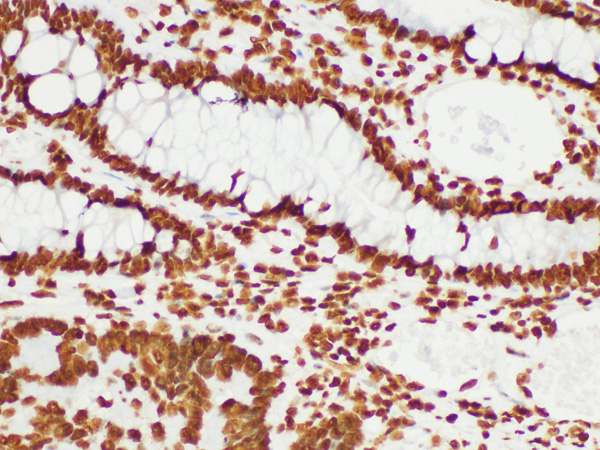

IHC (Immunohiostchemistry)

(Immunohistochemistry of paraffin-embedded Human colon cancer using Histone H3 Polycloanl Antibody at dilution of 1:200.)